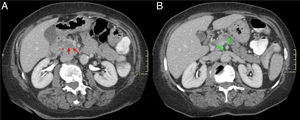

Mujer de 65 años con diarrea crónica. Cortes axiales del abdomen tras administración de CIV en fase portal (A y B). Tenue hipodensidad en la cabeza-proceso uncinado del páncreas que contacta con la vena mesentérica superior (flechas rojas, A). Dilatación de la vía biliar extrahepática y del CP (signo del doble conducto) (flechas verdes, B) y borramiento del surco pancreaticoduodenal (asterisco rojo, A). Hallazgos sugestivos de neoplasia de páncreas.

Mismo paciente de la Figura 9. Cortes axiales del abdomen en secuencia T1 FS poscontraste (VIBE). A y B) Masa hipointensa en cabeza pancreática respecto al resto del páncreas con ocupación del surco pancreaticoduodenal (flecha y asterisco rojos, A) y dilatación de vía biliar extrahepática y del CP (flechas verdes, B). El diagnóstico final fue de adenocarcinoma de páncreas.

El engrosamiento de la pared del duodeno con estenosis luminal secundaria y quistes en su pared o en el surco son hallazgos infrecuentes en el ACP, cuya presencia haría inclinarse hacia el diagnóstico de PS. Sin embargo, la existencia de una masa hipointensa en T1 con invasión vascular, adenopatías o infiltración del retroperitoneo haría más factible el diagnóstico de ACP (figs. 7 y 8)7,9,10. Otro hallazgo que diferencia el ACP de la PS es una dilatación, tanto del CPP como del colédoco (signo del doble conducto) (figs. 9 y 10)8. El patrón de realce de estas dos entidades en estudios poscontraste es también diferente y ayuda a diferenciar ambas entidades. El ACP presenta escaso realce y de forma homogénea, mientras que la PS suele realzar de forma tardía y heterogénea7.

Existen otros hallazgos radiológicos descritos que no ayudan a diferenciar la PS del ACP, como, por ejemplo, la dilatación del CPP o del colédoco, ya que, por localización anatómica, ambos se pueden ver afectados en las dos entidades2,3, aunque en casos de PS la estenosis del colédoco suele ser regular y lisa y en casos de ACP suele ser irregular y abrupta2.